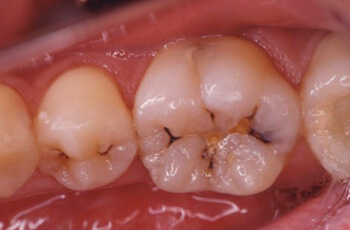

症例1:大、小臼歯の虫歯をセラミックインレーで修復しました。